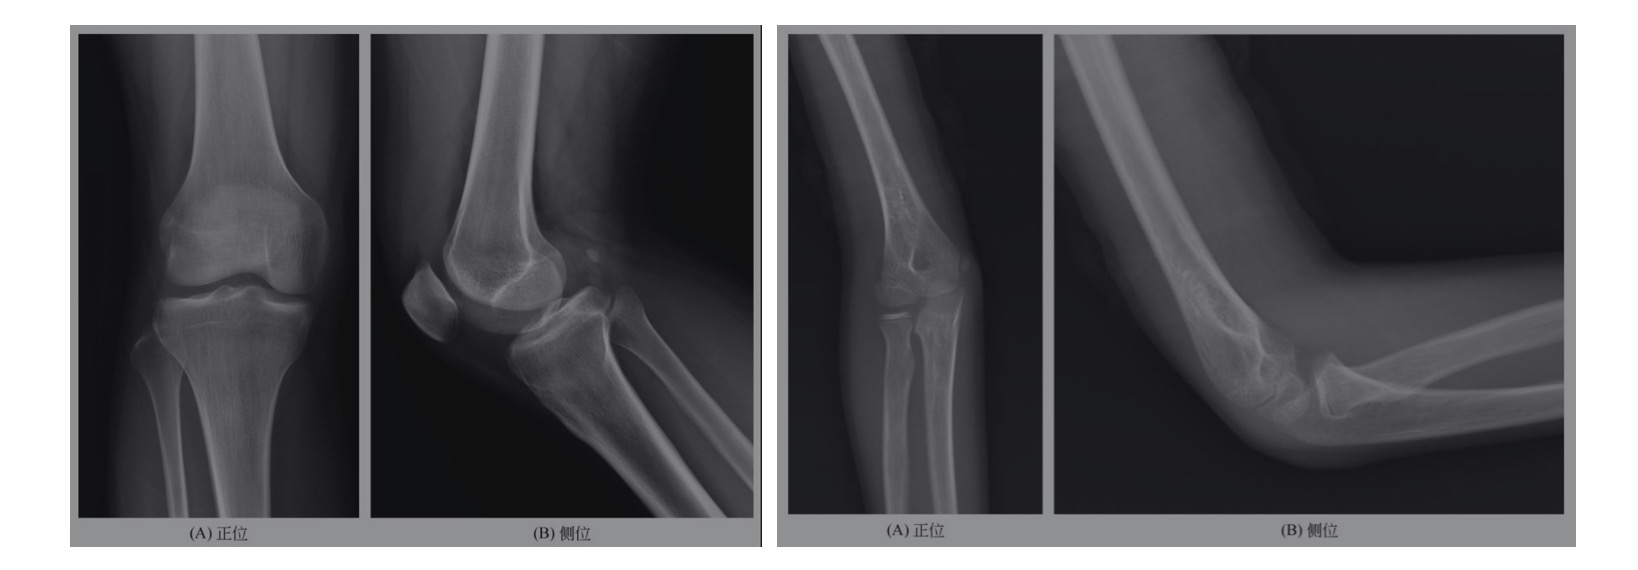

二、正常骨关节X线解剖及变异熟悉骨关节正常的X线解剖是骨肌系统疾病X线诊断的基础,而处于骨骼生长发育阶段的儿童,其正常骨骼表现与成人有所不同,应明确各部位骨化中心闭合的大致年龄,此外骨骼的生长变异较多,形态不一,如籽骨、副骨、骨嵴、血管沟、二次骨化中心不愈、邻近软组织结构牵拉及压迫等,有时与病变很难鉴别,必要时可加照对侧位并结合临床体征。正常成人骨关节见图5-1-

右膝关节组成各骨骨质形态、密度未见异常,骨骺及干骺端闭合,胫骨结节形态规则、愈合,关节面光整,关节间隙正常,周围软组织形态、密度未见异常。提示:用正位、侧位观察诸骨的骨质形态、密度及关节间隙有无异常;胫骨结节形态变异较多,必要时加照对侧对比;注意区别长骨血管沟及肌肉附着点的“拽曳”;软组织形态及密度改变对创伤有提示作用。

右肘关节组成各骨骨质形态、密度未见异常,桡骨小头及肱骨小头可见未闭合骨骺线,右肱骨内上髁可见骨骺影,关节面光整,关节间隙正常,周围软组织形态、密度未见异常。提示:应熟悉儿童正常骨骺大致闭合年龄。